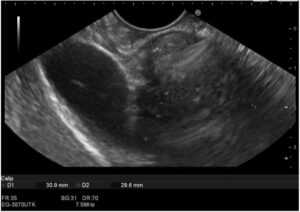

Endoscopic ultrasound (EUS) demonstrated a heterogeneous, predominantly hypoechoic lesion with extensive internal calcification, originating from the muscularis propria (Figure 1). EUS-guided fine needle biopsy (FNB) was performed, but histological examination was inconclusive, revealing fibromuscular tissue and focal mature adipocytes.

Figure 1: EUS image showing a heterogeneous calcified lesion.